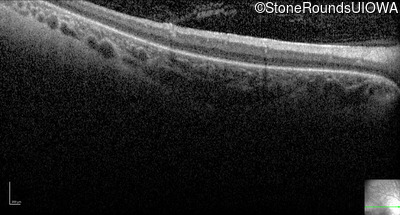

Optical Coherence Tomography - Left - No Light Perception

Exemplar / OCT Stack